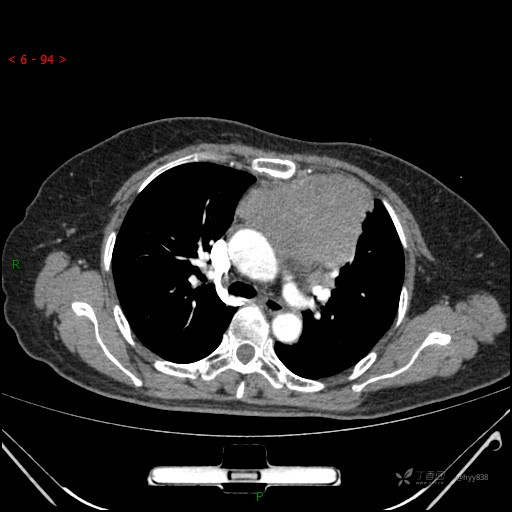

简要病史:患者诉3月余前患新冠肺炎,出现持续性胸闷,活动后可缓解,无胸前区压榨感,无畏寒发热不适,无胸痛咯血、呼吸困难,无恶心、呕吐,无腹痛、腹胀、腹泻等不适,未予以重视,未行特殊处理。患者胸闷持续存在,为进一步诊治,3天前于本院查胸部CT提示前纵膈团块状软组织密度影,肿瘤性病变可能,心包积液,左上肺磨玻璃结节,右下肺增殖灶可能建议进一步检查。门诊以“前纵膈占位” 收入我科。 患者本次起病来精神、食欲、睡眠尚可,大小便正常,体力、体重无明显变化。

辅助检查:CT

静脉期